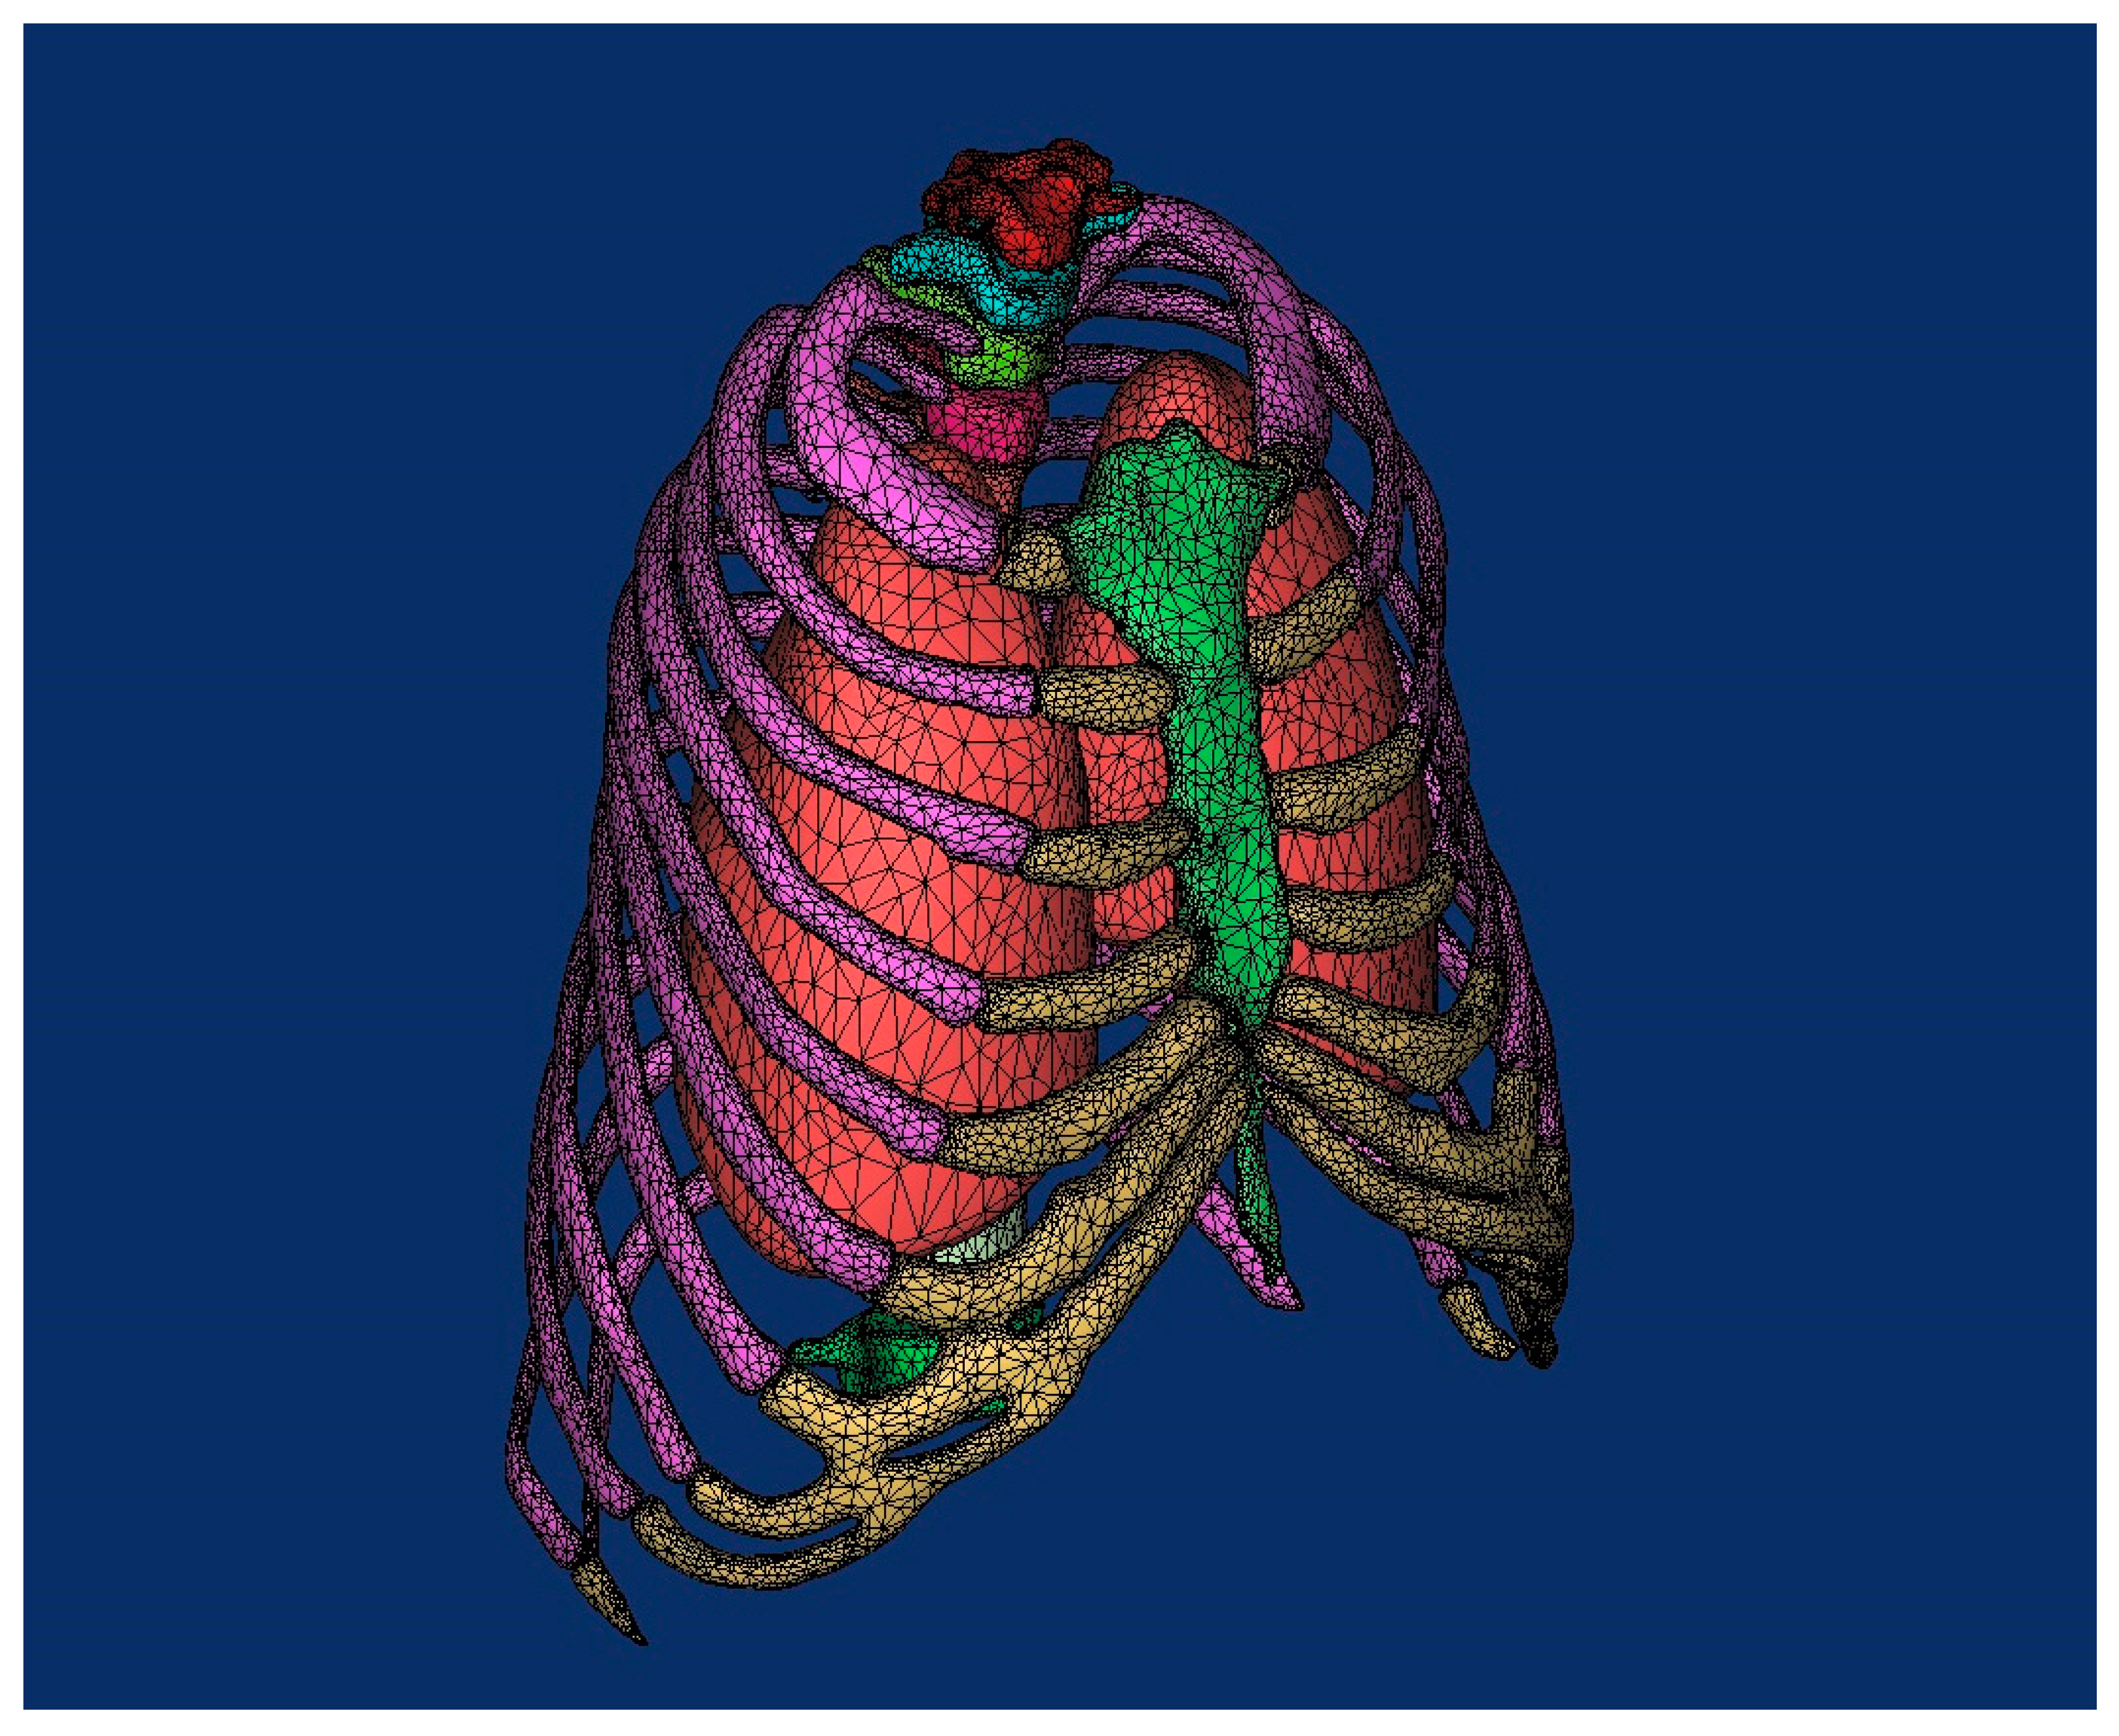

3. Reconstruction of the Damaged Human Model

4.1. Pre-Processing of Computational Numerical Analysis